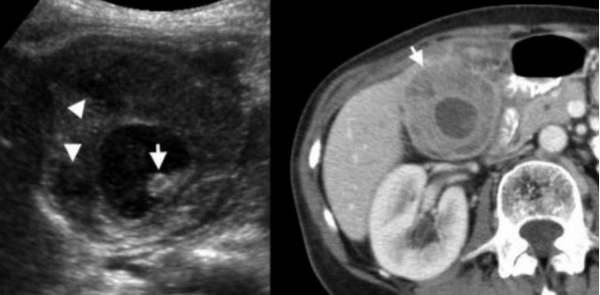

Ксантогранулематозный холецистит.

Ксантогранулематозный холецистит — это воспалительное заболевание, характеризующаяся тем, что в стенке желчного пузыря образуются ксантомы и гранулемы. При исследовании выявляют утолщение стенки желчного пузыря, уменьшение органа в размере, а также интрамуральные узелки, которые визуализируются, как гипоэхогенные включения на УЗИ и гиподенсные на компьютерной томограмме. Данные включения схожи с включениями при карциноме желчного пузыря.

УЗИ и КТ желчного пузыря. Ксантогранулематозный холецистит. Слева на УЗИ визуализируется (помечено стрелками) утолщение стенки желчного пузыря с интрамуральным включением и с камнем в просвете органа. Справа на КТ выявляется утолщение стенки с гиподенсными включениями.

Выше представлено КТ пациента 71 года с ксантогранулематозным холециститом. Постконтрастное КТ. Визуализируется утолщение стенки желчного пузыря с включениями, которые соответствуют абсцессу или фокусам воспаления.

КТ желчного пузыря/Рак желчного пузыря

Наиболее часто встречаемый рак желчного пузыря является карцинома. Карцинома желчного пузыря занимает пятое место по частоте встречаемости среди раков желудочно-кишечного тракта. Чаще его обнаруживают случайно (в 2% случаях) при гистологической проверке после холецистэктомии. Карцинома желчного пузыря выявляется на последних стадиях заболевания так, как себя не проявляет клинически на ранних. Специфических признаков при карциноме желчного пузыря также нет. Рак может поражать желчный пузырь диффузно, целиком стенку или пристеночно. Карцинома желчного пузыря имеет схожую картину с ксантогрануломатозным холециститом, но при постановке диагноза радиологу помогают такие находки:

- Прорастание в соседние органы.

- Вторичная дилатация желчных протоков.

- Метастазирование в печень или лимфатические узлы.

УЗИ (слева) и КТ (справа) желчного пузыря. На УЗИ ярко выраженное утолщение стенки желчного пузыря (указаны белыми стрелками). Множественные камни в просвете желчного пузыря (указано стрелкой). Компьютерная томография с контрастным усилением. На КТ визуализируются утолщение стенки с внутристеночными гиподенсными включениями. На КТ также выявлено, что процесс распространился на печень (указано стрелкой).